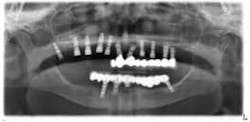

An 81-year-old female with stent placement 10 years ago taking no medications presented with a chief complaint that her old prosthesis broke, and she cannot chew and function. She had a previous bridge consisting of an implant in the No. 1 site combined with the natural teeth and implants in the 8, 9, 14, 15. No. 8, 9 implants were malpositioned with a 35-degree angle and significant mucogingival defects.

Various treatment options were explained to the patient, and a treatment plan consisting of Coldwell-Luc external sinus lift with bilateral block placement in area 5 to 7 and 10 to 12 was agreed upon.

Under local anesthesia, a full thickness flap was elevated from the upper right to upper left posterior segments. Using a piezoelectric handpiece, a buccal window hinge osteotomy was elevated in the maxillary right posterior region. A mixture of DFDBA, anorganic bovine bone, and PRF was placed. A collagen membrane was used to cover the buccal window. Simultaneously, two puros J-block allografts were secured in the 5 to 7 and 10 to 12 region with stainless steel screws (1.6 x 8 mm screws). A mixture of DFDBA, anorganic bovine bone and PRF was placed over each area and covered with PRF sheet and a collagen membrane. Primary closure was obtained with CV-5 Goretex sutures. Healing was uneventful. After six months of healing, six straight implants were placed in sites 3, 4, 5, 6, 11, and 12. Healing abutments were placed at stage I. Healing was uneventful. After four months of healing, six custom abutments were fabricated by his dentist and cover screws were placed on implants 8 and 9 and converted into pontics.

Removing the implants would have created a large buccal defect, which would have created elongated pontics in the maxillary anterior region. The prosthesis was completed, and the patient is stable and highly appreciative of her ability to smile and chew.

Case 2: Sinus lift, bone graft, PRP, and after healing implant placement